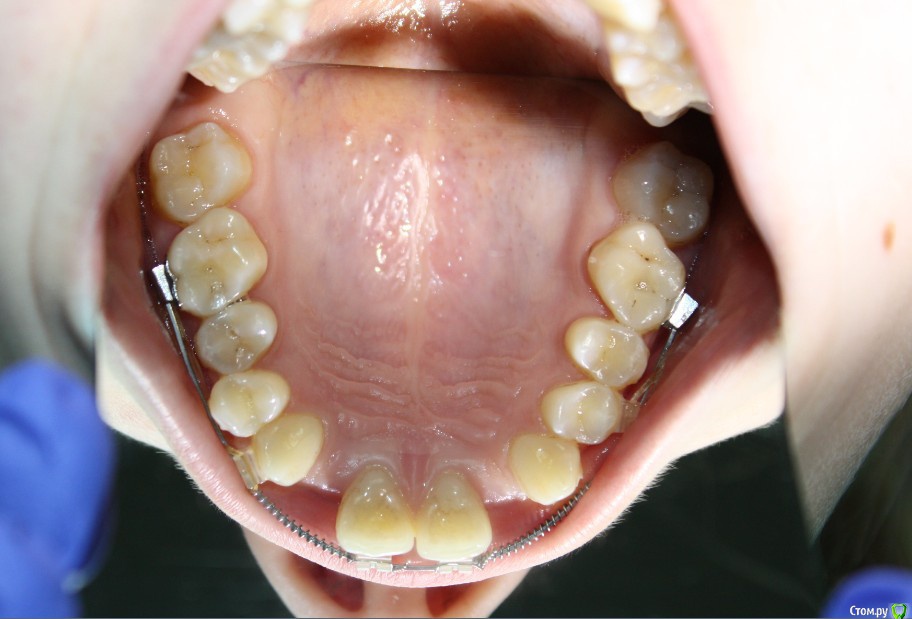

Здравствуйте коллеги! На консультацию обратилась пациентка, сейчас находится на ортодонтическом лечении. Предистория: три года назад обратилась к стоматологам с жалобой на неудовлетворительную эстетику фронтального отдела, вследствие врожденного отсутствия латеральных резцов. Ей было предложено ортодонтически создать место для боковых резцов, затем провести имплантацию и протезирование на имплантатах 12, 22.

Затем, с ее слов, идет длительный этап ортодонтии, почти 3 года, вследствие которого получили немного места для двоек, которого не достаточно для иплантации, так же центральные резцы ушли вперед, образовалась саггитальная щель.

Фото сегодня:post-461-0-94195200-1456407270_thumb.jpgpost-461-0-97652100-1456407271_thumb.jpgpost-461-0-40898500-1456407273_thumb.jpgpost-461-0-68973300-1456407274_thumb.jpgpost-461-0-88108800-1456407275_thumb.jpgpost-461-0-99061300-1456407276_thumb.jpgpost-461-0-92547500-1456407277_thumb.jpgpost-461-0-02811200-1456407279_thumb.jpgpost-461-0-05035300-1456407280_thumb.jpgpost-461-0-27197600-1456407281_thumb.jpg